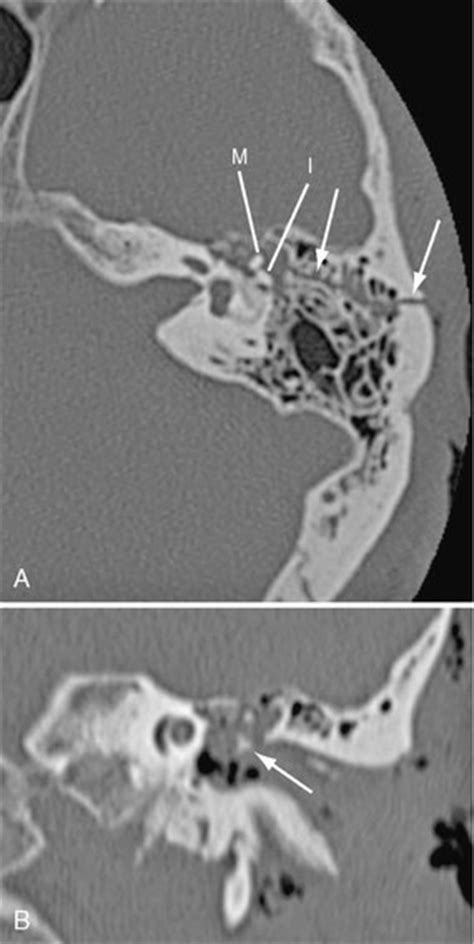

Growing skull fractures should be suspected in children younger than 3 years with a palpable mass. Growing skull fracture (gsf) is a rare complication of pediatric head trauma and causes delayed onset neurological deficits and cranial defect. Skull fracture in infancy or early childhood which results in dural tear and brain injury can.

@article{djientcheu2005growingsf, title={growing skull fractures}, author={v. It is important that an infant with a diastatic fracture are monitored for a growing fracture. The typical features of a growing skull fracture are discussed. Growing skull fractures are rare complications of head injury in young children. They are most common in the. In two children with growing fractures, underlying cerebral injury resulted in focal motor signs or convulsions. In severe cases, some infants may develop permanent brain damage, a key cause for numerous debilitating disorders. Gsf usually develops following linear fracture. Severe skull fractures in newborn children are rare and serious. Growing skull fracture (leptomeningeal cyst). A rare sequel to a cranial fracture, especially in the parietal region, in which the cranial fracture grows following lacerations involving the dura mater. Growing skull fracture or craniocerebral erosion is a rare complication of linear skull fracture in childhood. A growing skull fracture (gsf) is a rare but significant late complication of skull fractures, usually occurring during infancy and early childhood. Growing skull fracture of the posterior cranial fossa and of the orbital roof. • fracture line is transverse the full thickness of the skull from the outer to inner table. A clinical study of 41 patients. Growing skull fracture are a complication which occurs after a few months of severe head injury which clinically presents with dizziness and ataxia.